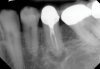

Just as systemic conditions and patient habits impact outcomes after NSRCT, the local dental environment and dental disease states also impact outcomes (Figure 1 through Figure 5). In the Toronto study evaluating 4- to 6-year outcomes following NSRCT, the presence of a periapical radiolucency emerged as a key prognostic factor, substantially reducing the success rate by a factor of four.12 Single-rooted teeth experienced better outcomes compared to multirooted teeth in the presence of periapical lesions.1 Teeth diagnosed preoperatively with irreversible pulpitis or necrosis, in the absence of AP, showed a more favorable prognosis compared to those with preoperative AP.2

Fig 1. NSRCT can have high success, even with risk factors like periapical pathology associated, as depicted in this case presentation. Fig 1: Preoperative periapical radiograph showing AP. Fig 2: Preoperative CBCT. Fig 3: Immediate postoperative periapical radiograph. Fig 4: Three-month follow-up CBCT showing reduction of periapical radiolucency. Fig 5: One-year follow-up periapical radiograph showing resolution of periapical radiolucency.

Figure 1